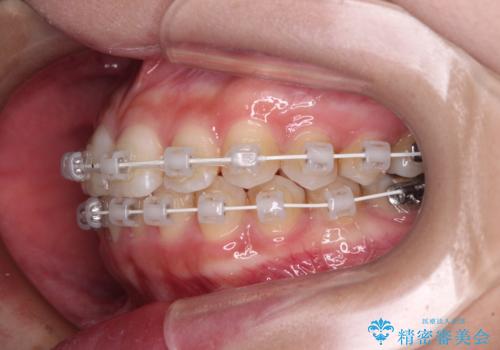

- 矯正装置

- 審美装置

- 歯並びと虫歯をきれいにしたいとのことで来院された患者様です。

楽して短期間で歯列を整えたいとのことで、ワイヤー装置を用いて矯正治療を行い、矯正治療後に下顎の虫歯はセラミックインレー、上顎はPGAインレー(ゴールドインレー)、根管治療を行う歯についてはオールセラミッククラウンにて補綴治療を行うこととしました。

矯正治療は8ヶ月ほどで終了し、速やかに虫歯治療に移行することができました。